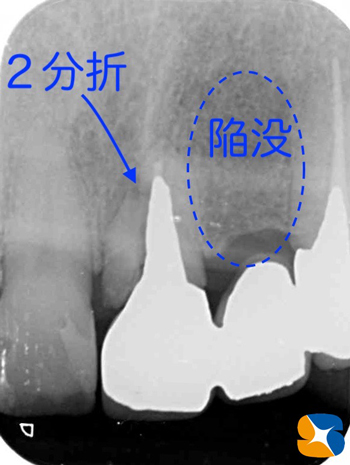

歯肉をはく離すると、歯根は2分折されていました。同時に周囲の骨も大きく衰退していました。

また隣の歯のない部分の骨は、かなり菲薄していましたので骨幅を2倍に増幅させたのち、インプラントを

移植することにしました。

折れた根を抜歯すると、根の先には大きな腫瘍が強固に付着していました。

かなり以前から、噛み合わせによるブリッジのトラブルが生じていたことが伺えます。

ブルーベリーサイズの骨の陥没が移植予定の中間地点にある。